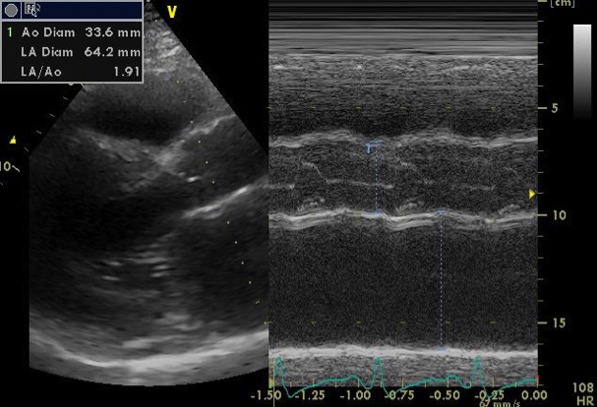

心エコー検査では、弁機能に異常なく、心嚢液の貯留はない。左房径(64mm)と左室径(60mm)は著明に拡張、左室は瀰漫性に壁運動の低下(EF=20%)。左室壁は中隔厚(18mm )、左室後壁厚(21mm)と共に肥厚しており、長年の左室圧負荷に加え、左室の収縮不全を認めることから、高血圧性心疾患に加え何らかの心筋疾患の可能性も否定できない。

心エコー画像1

心エコー画像2

心エコー画像3